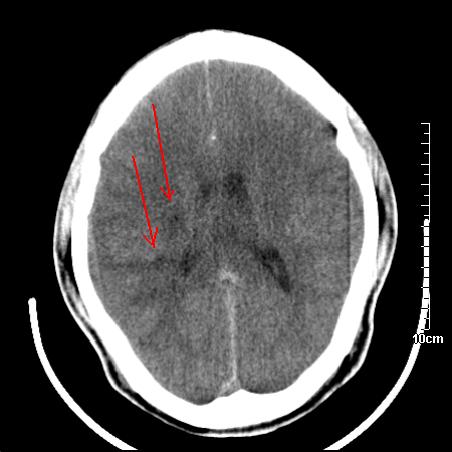

头晕.头痛间断意识恍惚1周 m/21y

4天上述症状加重伴左侧肢体发软,复查ct,

右側额叶、放射冠区灰白质改变,建议ct增强或mri检查

右侧放射冠区混杂密度灶,边缘不清,病人较年轻,结合有发热病史,支持感染性病变,建议密切结合临床可抗感染治疗后复查。

右侧颞叶病变定性困难,既然发病急,又有发热,脑脓肿不能除外。

右侧颞叶混杂密度灶,强烈建议:增强ct检查